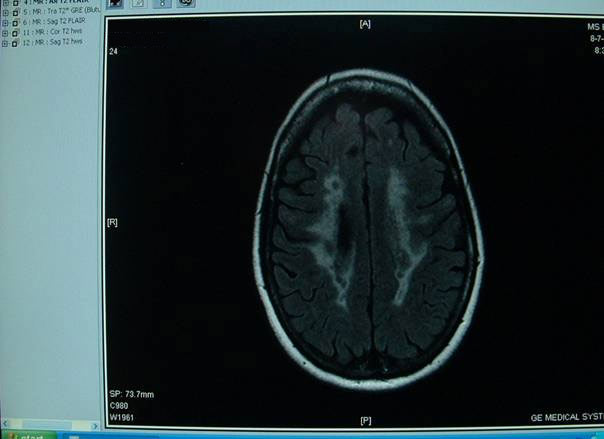

Als eerste kreeg Annet een MRV (dat is gelijk aan een MRI) helemaal vast gebonden

zodat ze geen kant op kon, is natuurlijk belangrijk anders moet het weer over gedaan

worden.

Na een half uurtje (volgens Annet) in een bouwplaats te hebben gelegen en ik

(Jan) even

Na goed een half uur kregen we het nagesprek met Dokter Kraus hij bevestigde dat

Annet twee vernauwingen heeft een die links erg dicht zit en de ander aan de rechter

kant die al lekker op begon te schieten dus die moet dan ook gedaan worden.

Hieronder enkele foto’s van de vernauwing.